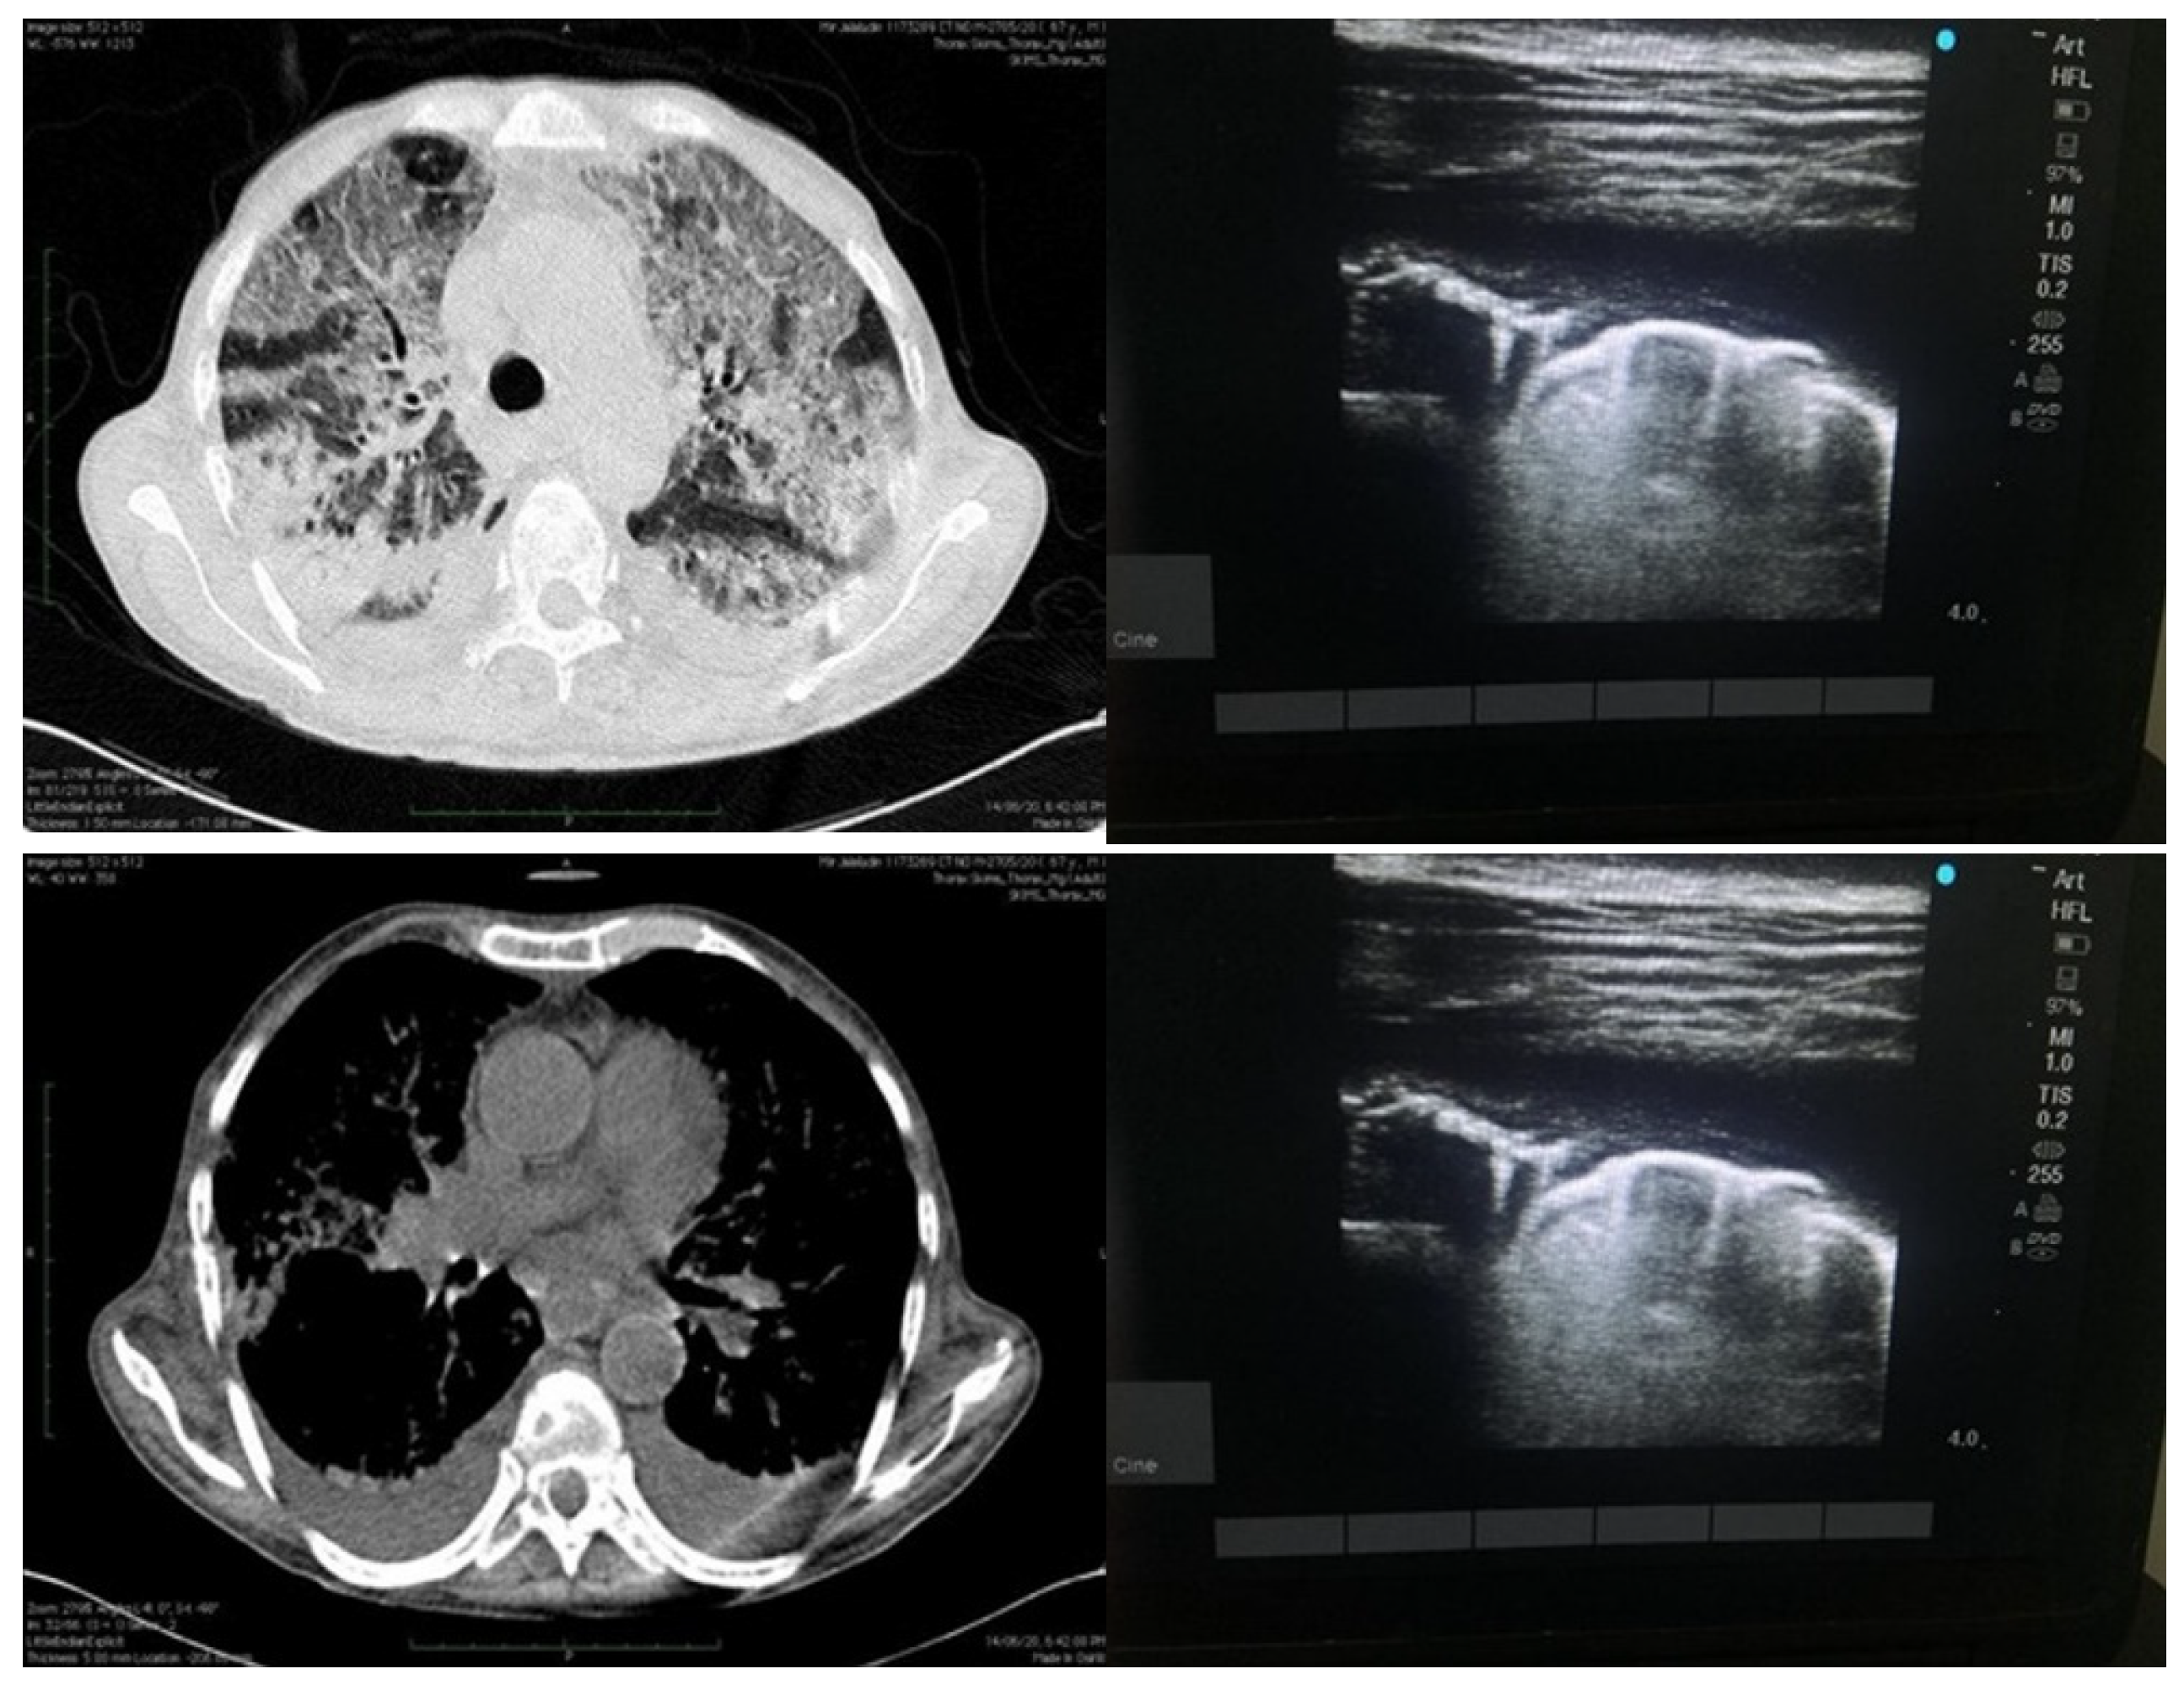

An experienced sonologist who had knowledge of performing and elucidating LUS performed all the examinations. The LUS exam was carried out in accordance with a 12-zone protocol. Careful evaluation was done to look for pleural effusions, confluent B-lines (CBL), isolated B-lines (IBL), irregular pleural line (IPL) and consolidations (Figure 2 and Figure 3). Both halves of the chest were scanned on their anterior, lateral and posterior aspects. These 12 zones were evaluated for the isolated B-lines (1 point), confluent B-lines (2 points) and consolidations or pleural effusion (3 points) with score range from (0–3). By summing the scores of all 12 zones the total lung score was achieved (range of possible scores: 0–36).

Figure 3.

Depicting findings of LUS on right side (above and below) as effusion with irregular pleural line and isolated B-lines and finally small effusion with isolated B-lines as well as confluent B-lines. Image on the left side depicts same patient with HRCT findings of consolidations as well ground glass opacities and pleural effusion.

Pattern of B-lines, either solitary and/or confluent, an uneven pleural line, and subpleural consolidations are all regarded as imaging signs of a compatible LUS exam. LUS examinations were performed using a GE Logic p5 USG machine, using a curvilinear array transducer and lung/cardiac pre-set. The sonologist performing the scan was blinded to all clinical details and HRCT findings.